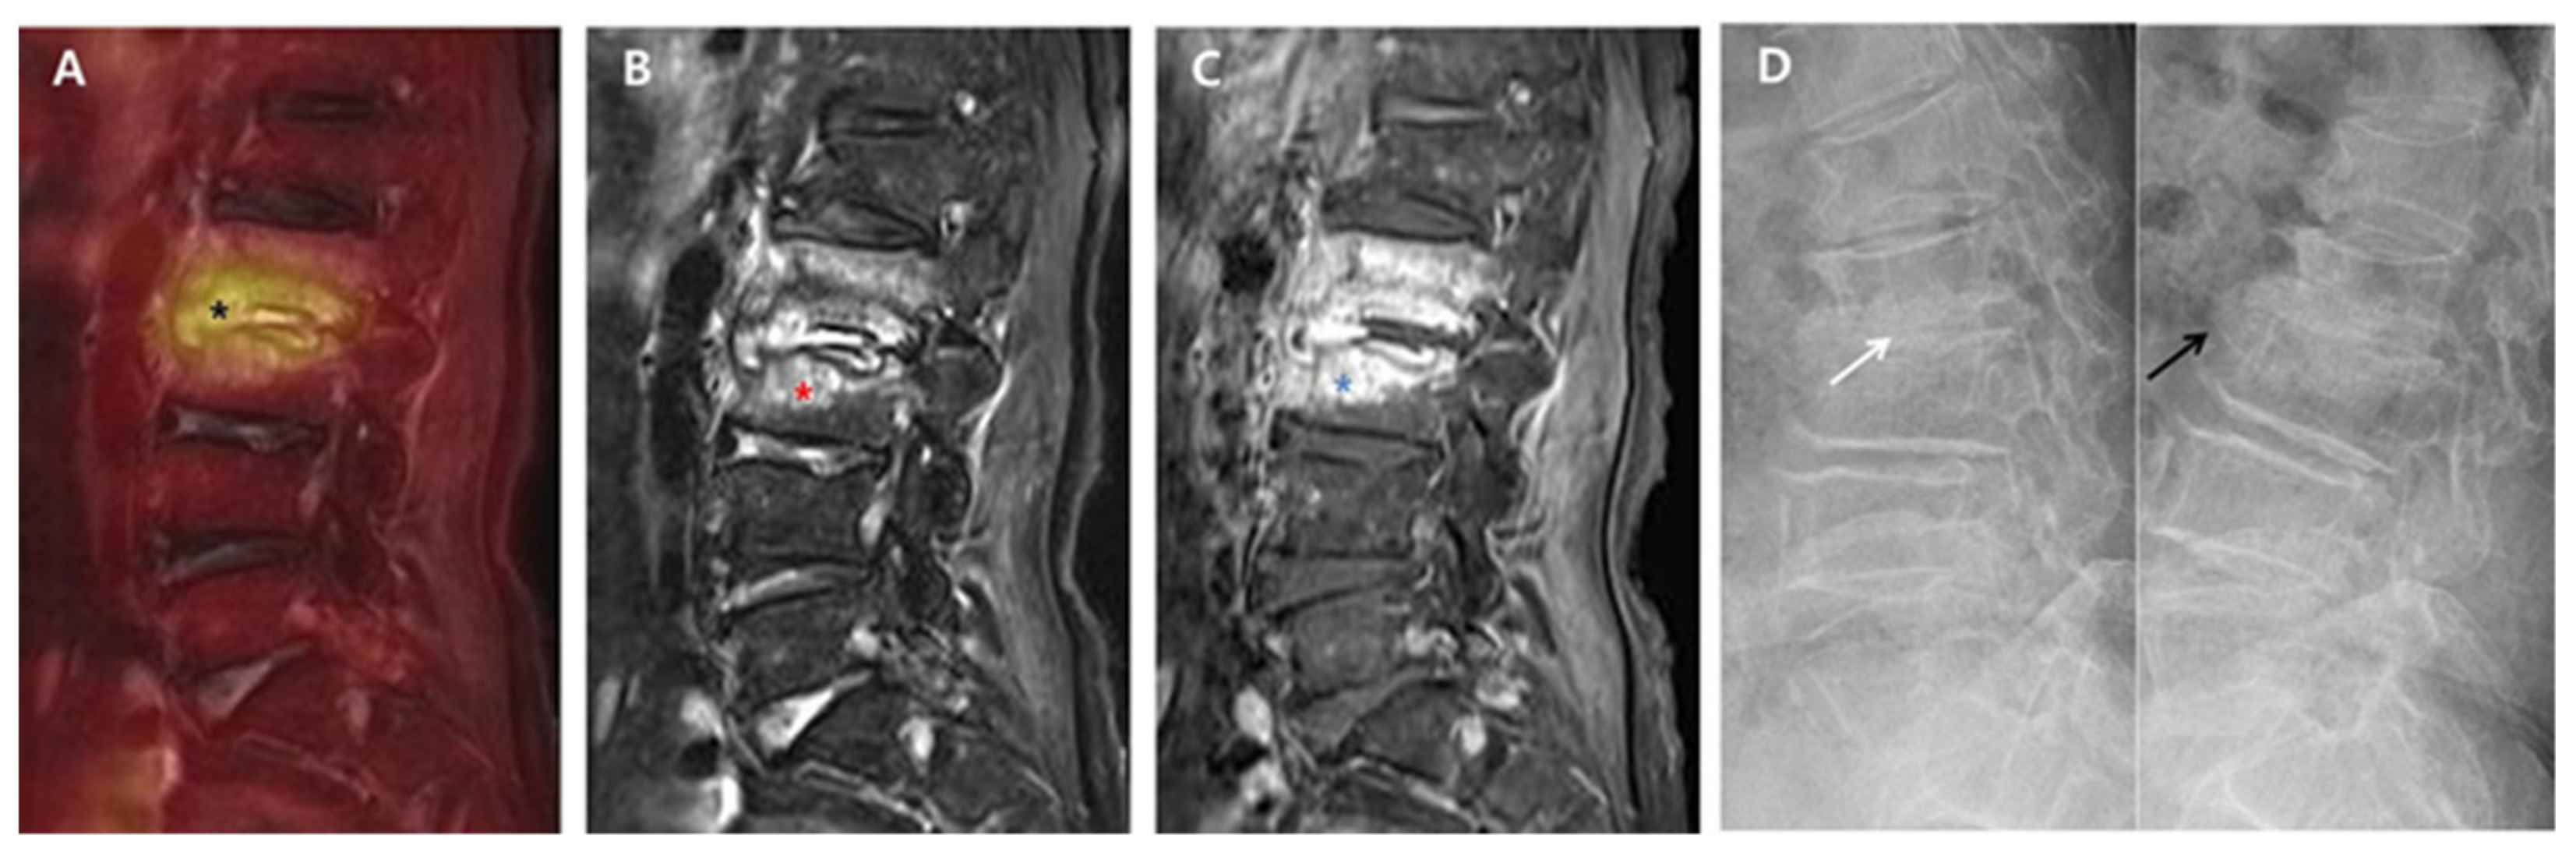

Back pain caused by the destruction of intervertebral discs and endplates may continue during the post-treatment course of PVO even after successful antibiotic therapy. Although some PVO lesions presenting back pain related with sustained instability may require additional fusion surgery, this study showed that most PVO lesions were stabilized with intervertebral autofusion or maintained joint function without any instability after successful antibiotic therapy. At 6-month follow-up, intervertebral autofusion was achieved in 59.3% of patients, and instability was identified in only 6.2% (2/32) of patients. However, there is still insufficient literature on the rate of autofusion or instability requiring surgical treatment. In this study, 14 patients were excluded because of insufficient radiological data at six-month follow-up, which can be a major limitation in obtaining higher levels of evidence; however, no patient was treated with additional fusion surgery. Hence, we can suggest that a large portion of intervertebral damage caused by PVO can be treated with intervertebral autofusion or preserved as an intervertebral joint after successful antibiotic therapy. Compared to group B with no intervertebral autofusion at six-month follow-up, group A with intervertebral autofusion showed more extensive edematous changes to vertebral bodies and a higher 18F-FDG uptake on the intervertebral structure immediately after antibiotic therapy (Figure 1 and Figure 2).

Figure 1. 18F-FDG-PET/MRI immediately after successful antibiotic therapy and radiographs at six-month follow-up in a patient with autofusion (group A). A 78-year-old female patient shows PVO of L2–3 on 18F-FDG-PET/MRI with SUVmax 5.03 of the intervertebral structure (black asterisk) after 56 days of ceftriaxone (ESR 71 mm/h and CRP 0.67 mg/dL). In the distribution pattern of the PVO lesion, 18F-FDG uptake (black asterisk) on 18F-FDG-PET (A) is limited on the damaged disc and endplates (grade II). However, T2FS MRI (B) and T1C MRI (C) show significantly increased high signal intensity (red asterisk) and contrast enhancement (blue asterisk) on the overall PVO lesion (grade III), respectively. On the dynamic radiographs at six-month follow-up (D), stable intervertebral structure presenting with the formation of syndesmophyte (black arrow) is noted with no intervertebral gap (white arrow). 18. F-FDG-PET/MRI, 18F-fluorodeoxyglucose positron emission tomography/magnetic resonance imaging; SUVmax, maximum standardized 18F-FDG uptake value; PVO, pyogenic vertebral osteomyelitis; CRP, C-reactive protein (normal range of < 0.5 mg/dL); ESR, erythrocyte sedimentation rate (normal range of <25 mm/h); T2FS, T2-weighted fat saturation; T1C, T1-weighted contrast; MRI, magnetic resonance imaging.